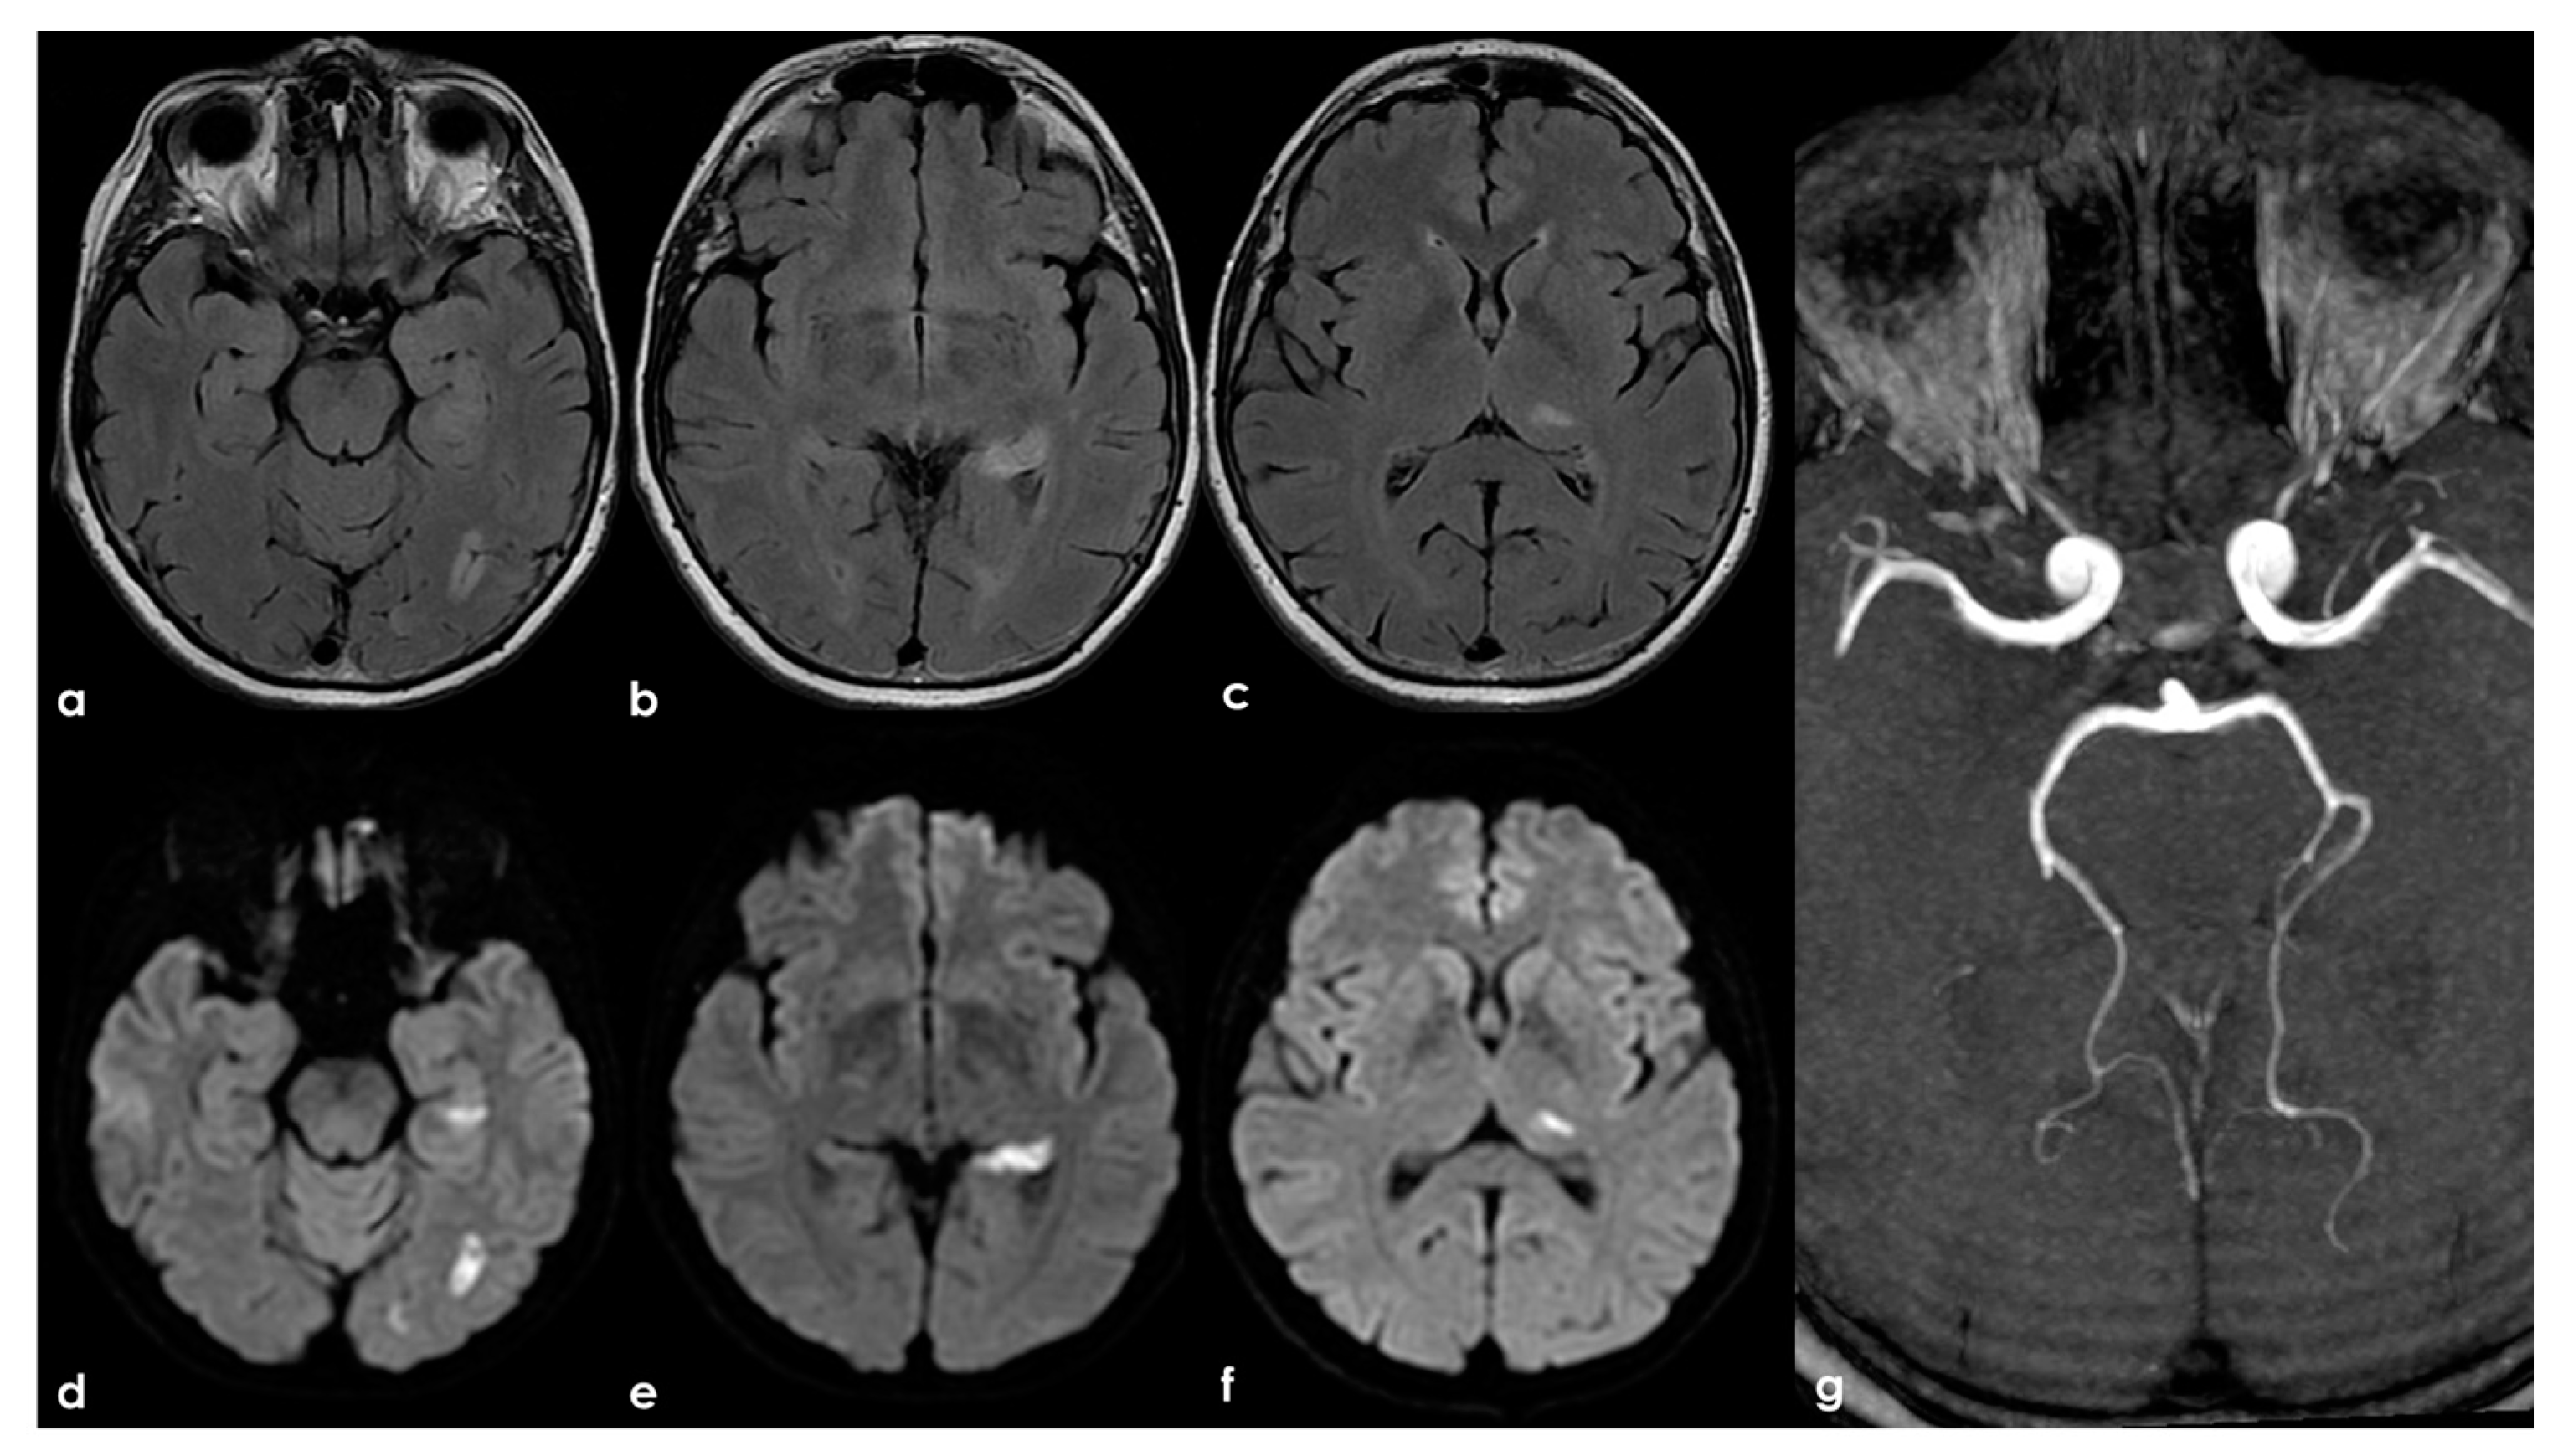

4.2.4. SLE with APS